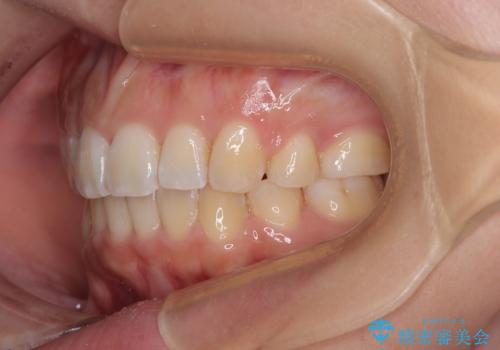

八重歯と上顎前突 ワイヤー装置での抜歯矯正

上下の前歯が接触する仕上がりとなったので、横顔の印象が大幅に改善されました。

- 八重歯と、上下前歯が接触しないくらい前突した前歯を気にして来院された患者様です。

口元の突出感を改善するために上下左右の小臼歯4本を抜歯し、ワイヤー装置によりデコボコを解消しながら口元の突出感も改善していくこととしました。